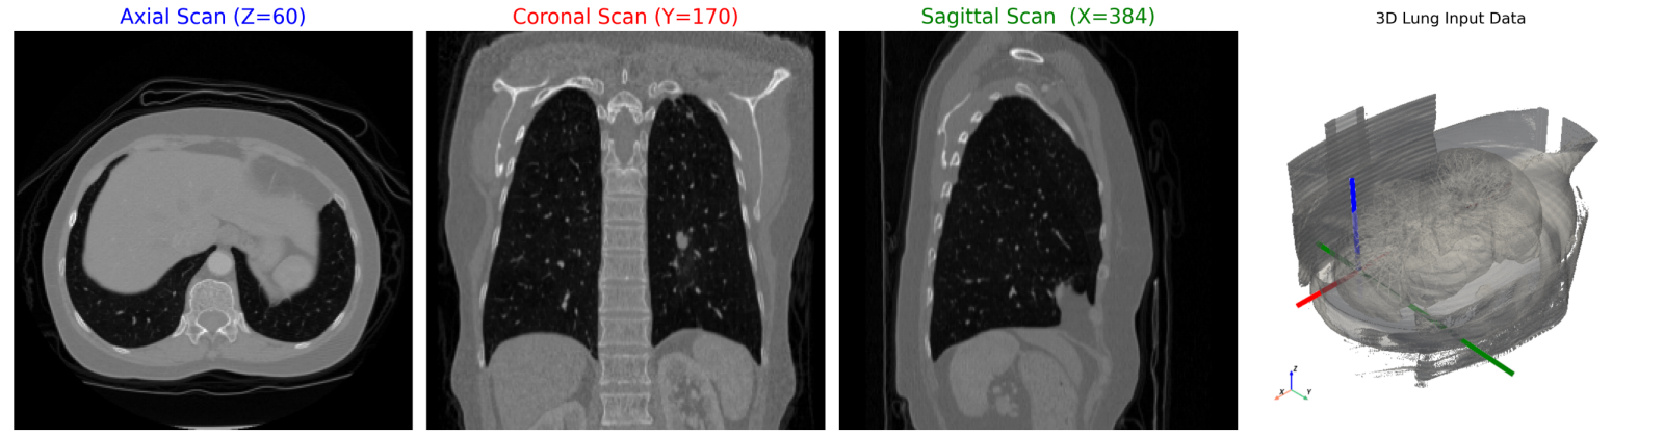

Axial, Coronal, and Sagittal slices with 3D volume overlay showing directional axes.